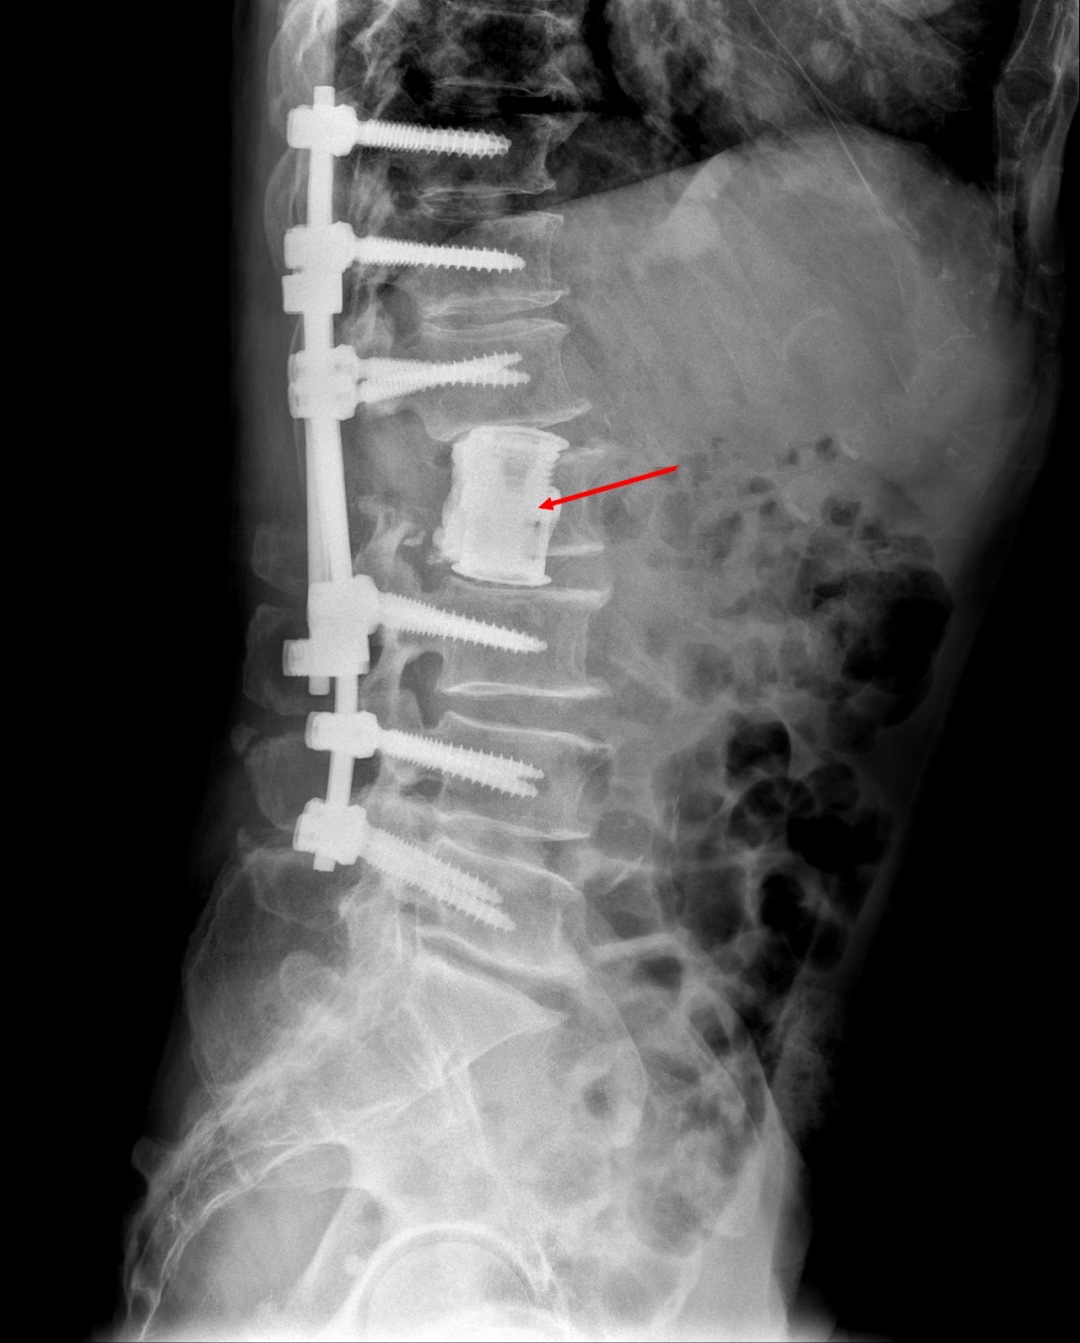

术前,为了安全起见,专家团队进行了充分的术前准备。术中,对两位患者的病变椎体进行了分离手术。为了防止术后脊柱塌陷,两节椎体之间用人工椎体支撑重建,钉棒系统固定,加强稳定性。整个手术非常顺利,术后予对症治疗后患者恢复良好。

手术后